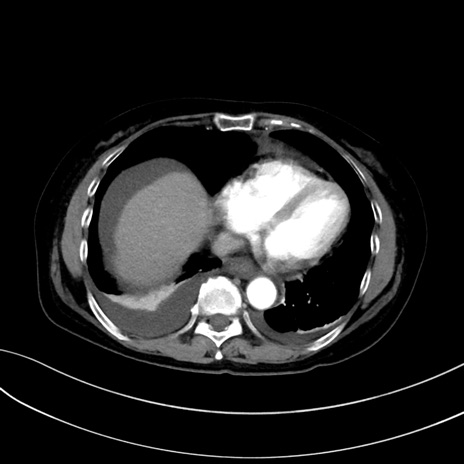

症例13 CT(横断像)1日半後